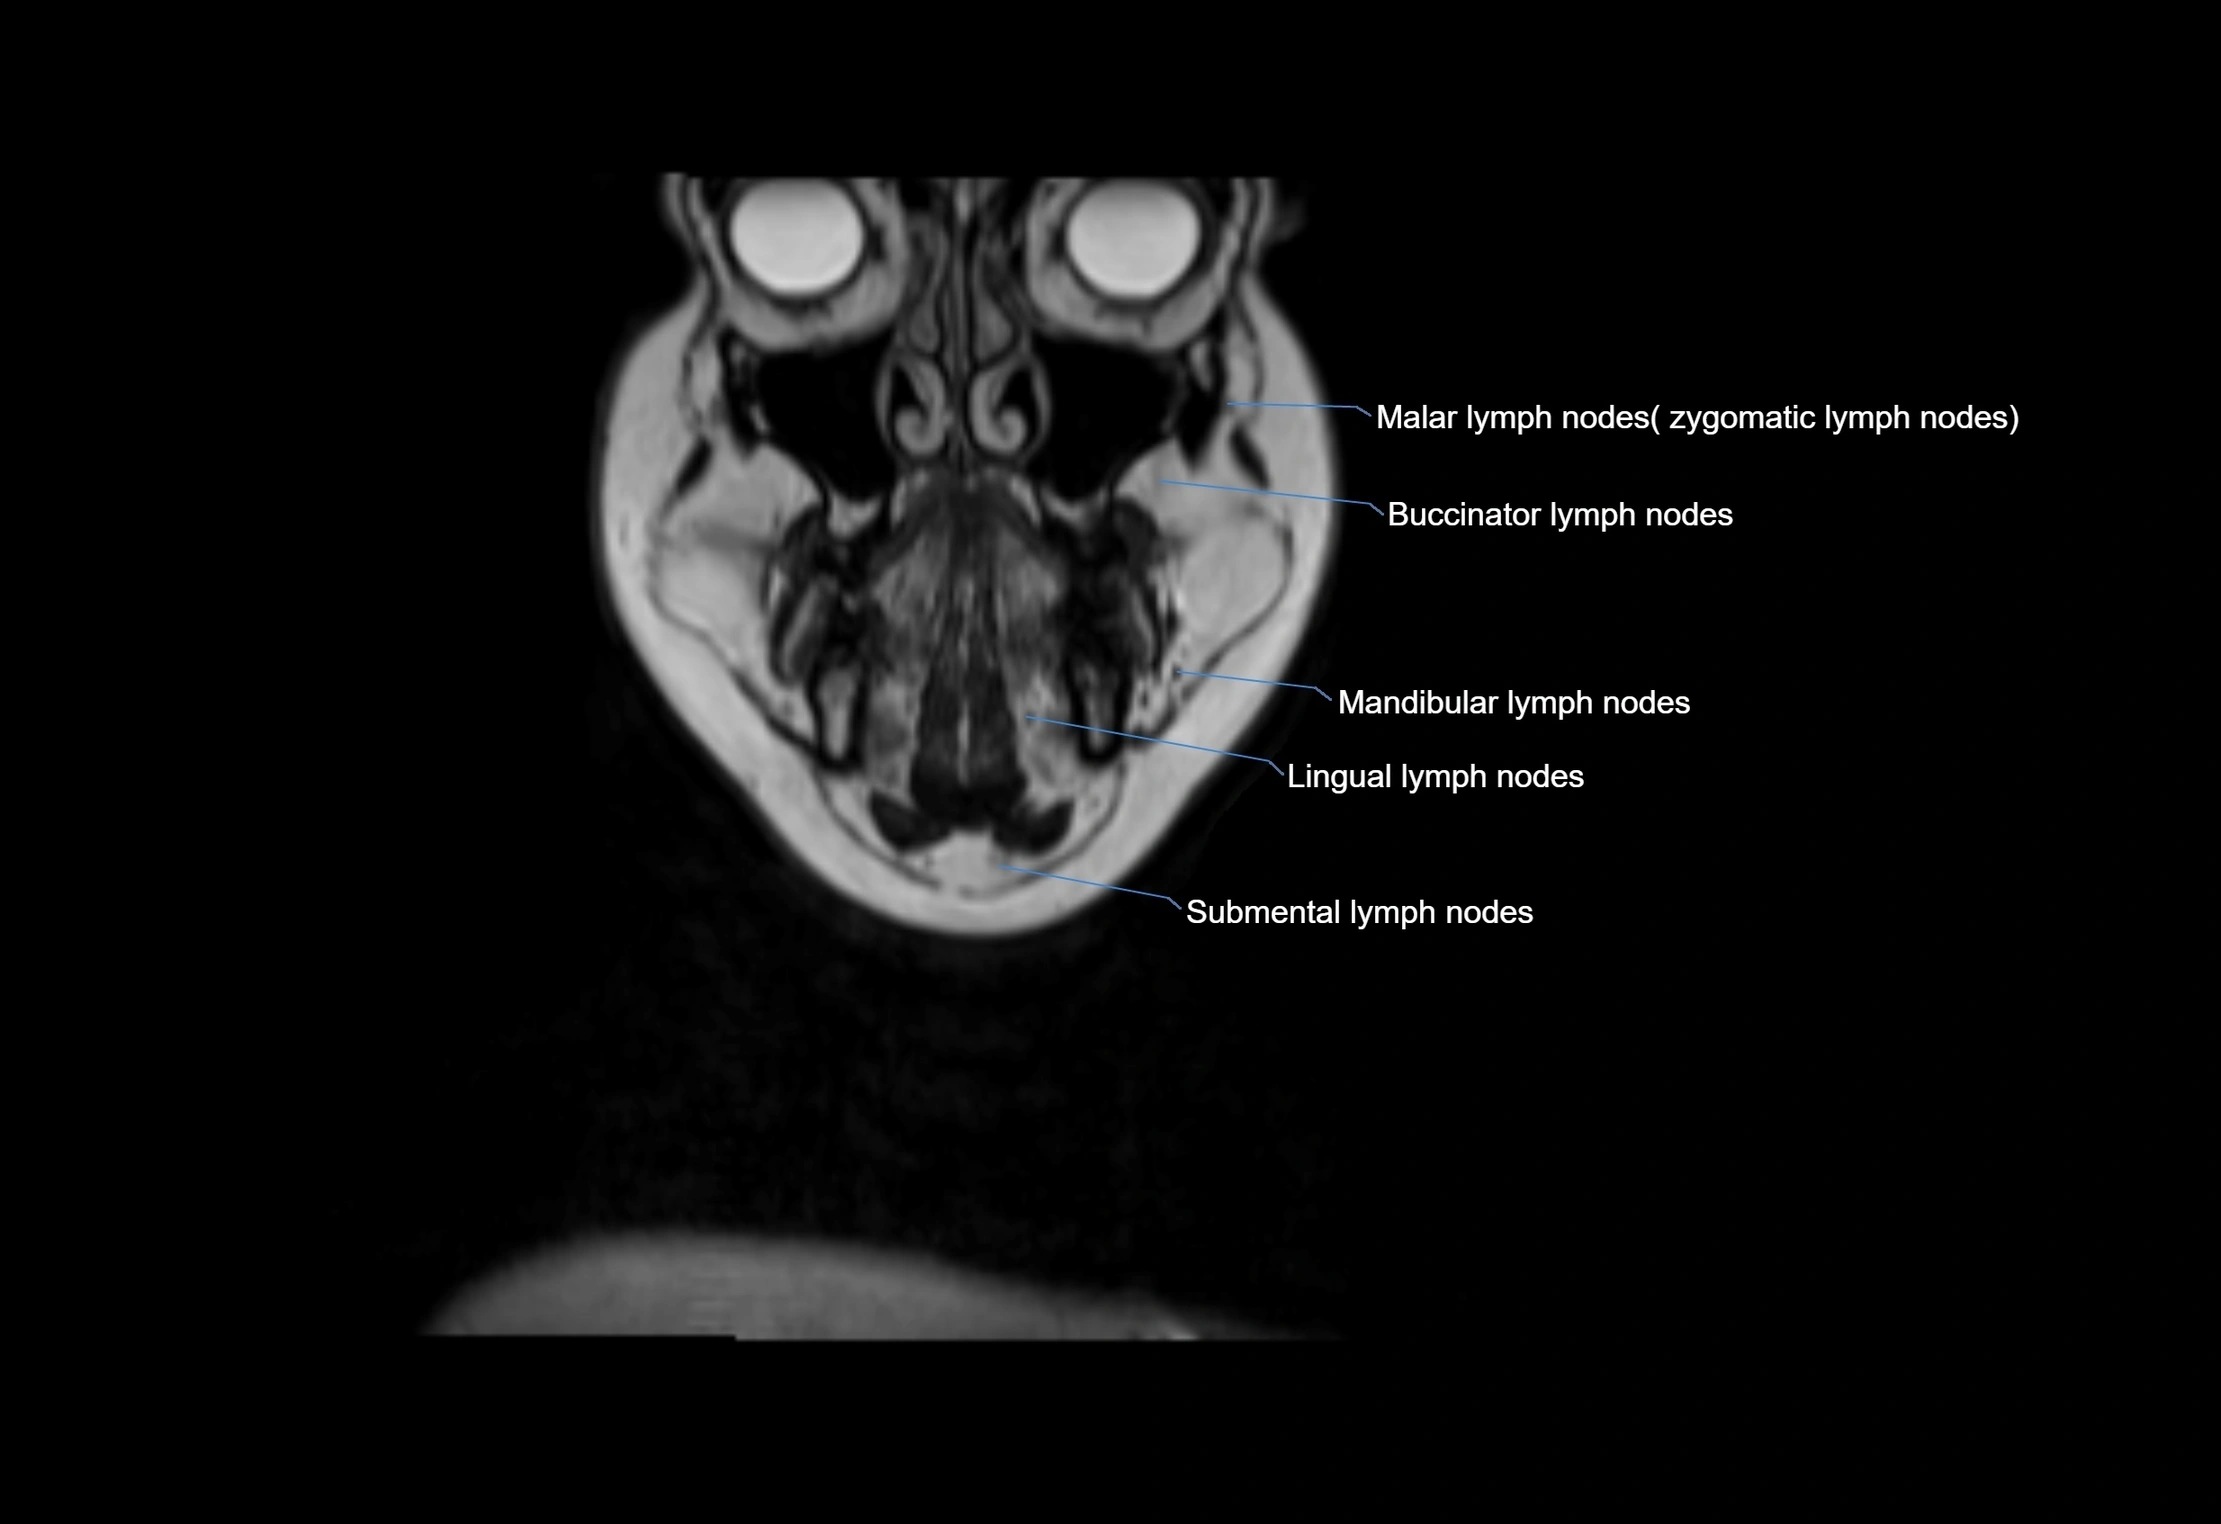

Accessory lymph nodes are small, secondary lymph nodes located along the main facial and cervical lymphatic chains, often adjacent to primary lymph nodes, such as preauricular, submandibular, or occipital nodes. They are typically less than 5 mm in diameter, embedded within subcutaneous fat or connective tissue, and may be variable in number and location. These nodes provide additional filtration and immune surveillance for lymph collected from the face, scalp, and neck regions. Accessory lymph nodes are usually non-palpable in healthy individuals but may enlarge in response to infection, inflammation, or metastasis, making them clinically significant.

Location

• Found along primary lymph node chains, including preauricular, submandibular, parotid, and occipital regions

• Embedded in subcutaneous fat or superficial fascia, often lateral or posterior to primary nodes

• Variable in number; may occur unilaterally or bilaterally, depending on individual anatomy

MRI images